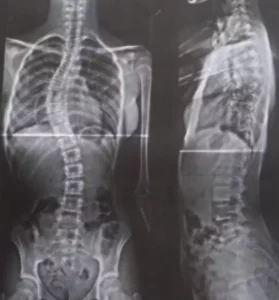

Segundo a mãe, ela já tentou atendimento pelo SUS quatro vezes, mas não encontrou profissionais especializados para o caso. Coluna da menina apresenta uma curva de 52 graus, considerada grave – Foto: Reprodução/acervo pessoal

Sophia Laborda, de 12 anos, foi diagnosticada com escoliose progressiva há dois anos. Desde então, a doença avançou e a curvatura da coluna chegou a 52 graus, um quadro considerado grave. A menina recebeu ajuda de médicos para realizar exames, mas a cirurgia só foi indicada na rede particular.

As cirurgias são indicadas quando há progressão que ultrapassa 40-45 graus. Por ser um procedimento invasivo, é meticulosamente programado, com avaliações pré- anestésicas, monitorização neurofisiológica (monitoramento da medula, na qual protege a parte de mobilidade) e dura em torno de duas horas e meia a três horas.